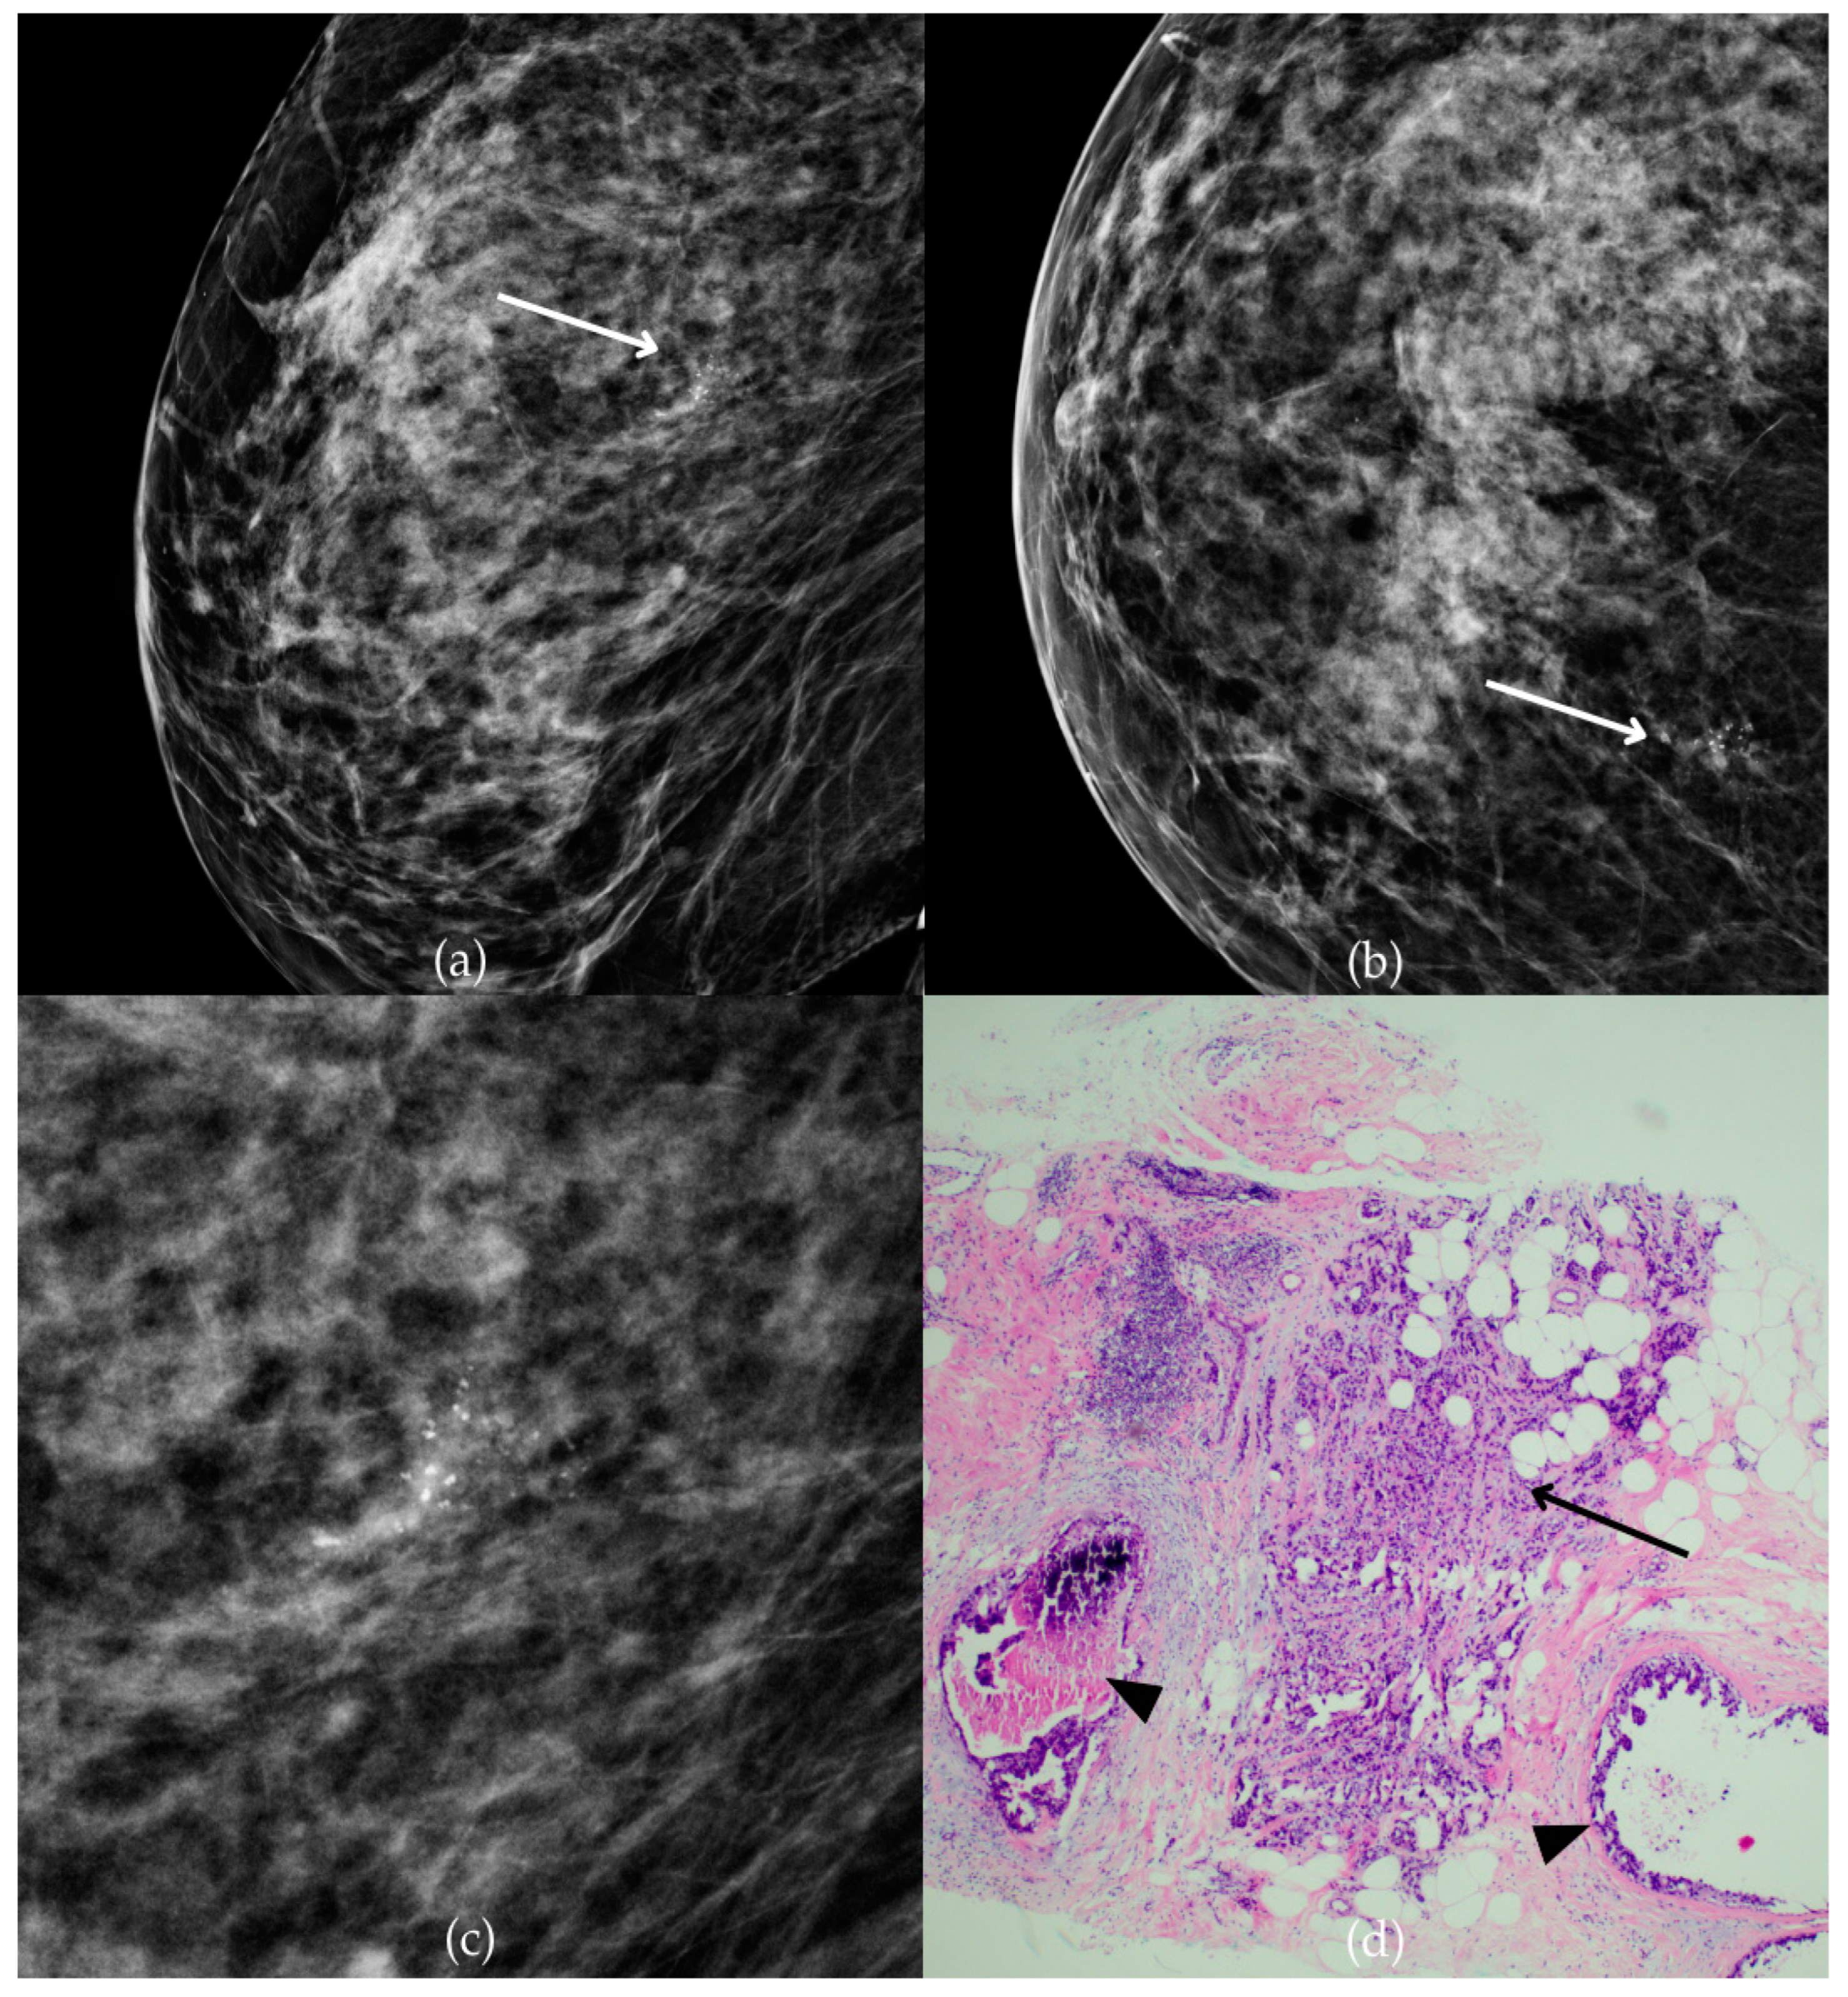

Figure 5 presents mammographic and histopathological images of a 56-year-old patient. The mammogram of the patient’s left breast shows architectural distortion within which there are fine pleomorphic calcifications with linear distribution in the lower inner quadrant, corresponding to a BI-RADS 4 finding. Tissue analysis obtained through biopsy indicated the presence of DCIS (category B5a). The patient underwent a mastectomy, and postoperative pathology detected invasive carcinoma.

Ductal carcinoma in situ (DCIS). (a) Mediolateral oblique (MLO) view; (b) craniocaudal (CC) view of the left breast showing architectural distortion with associated fine pleomorphic calcifications (marked with arrows) in the lower inner quadrant, with a linear distribution. (c) Magnified mammographic image of fine pleomorphic calcifications with a linear distribution within architectural distortion. (d) The histopathological image of the biopsy sample shows the characteristic features of DCIS (HE staining; 40× magnification).